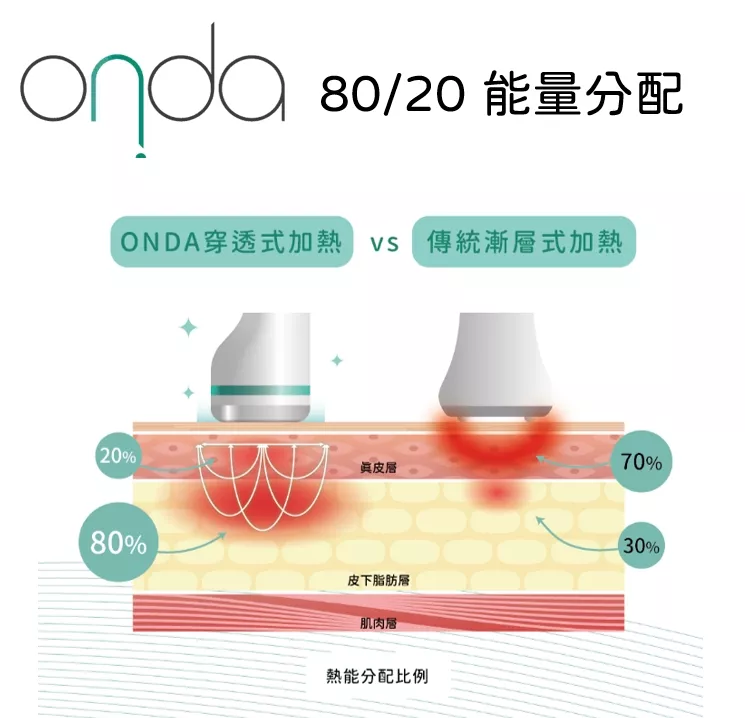

ONDA PRO 昂達超微波穿透式加熱優點

80% 能量優先被皮下淺層脂肪吸收,深層加熱升溫快速

20% 能量由表真皮層吸收,緊緻皮膚,同時有冷卻系統保護表皮不會燙傷

20% 能量由表真皮層吸收,緊緻皮膚,同時有冷卻系統保護表皮不會燙傷

穿透加熱

超微波新式科技穿透式加熱,快速穿透表皮層與真皮層,2.45GHz 促進深層脂肪持續加熱時,對組織產生80/20之熱能分配法則